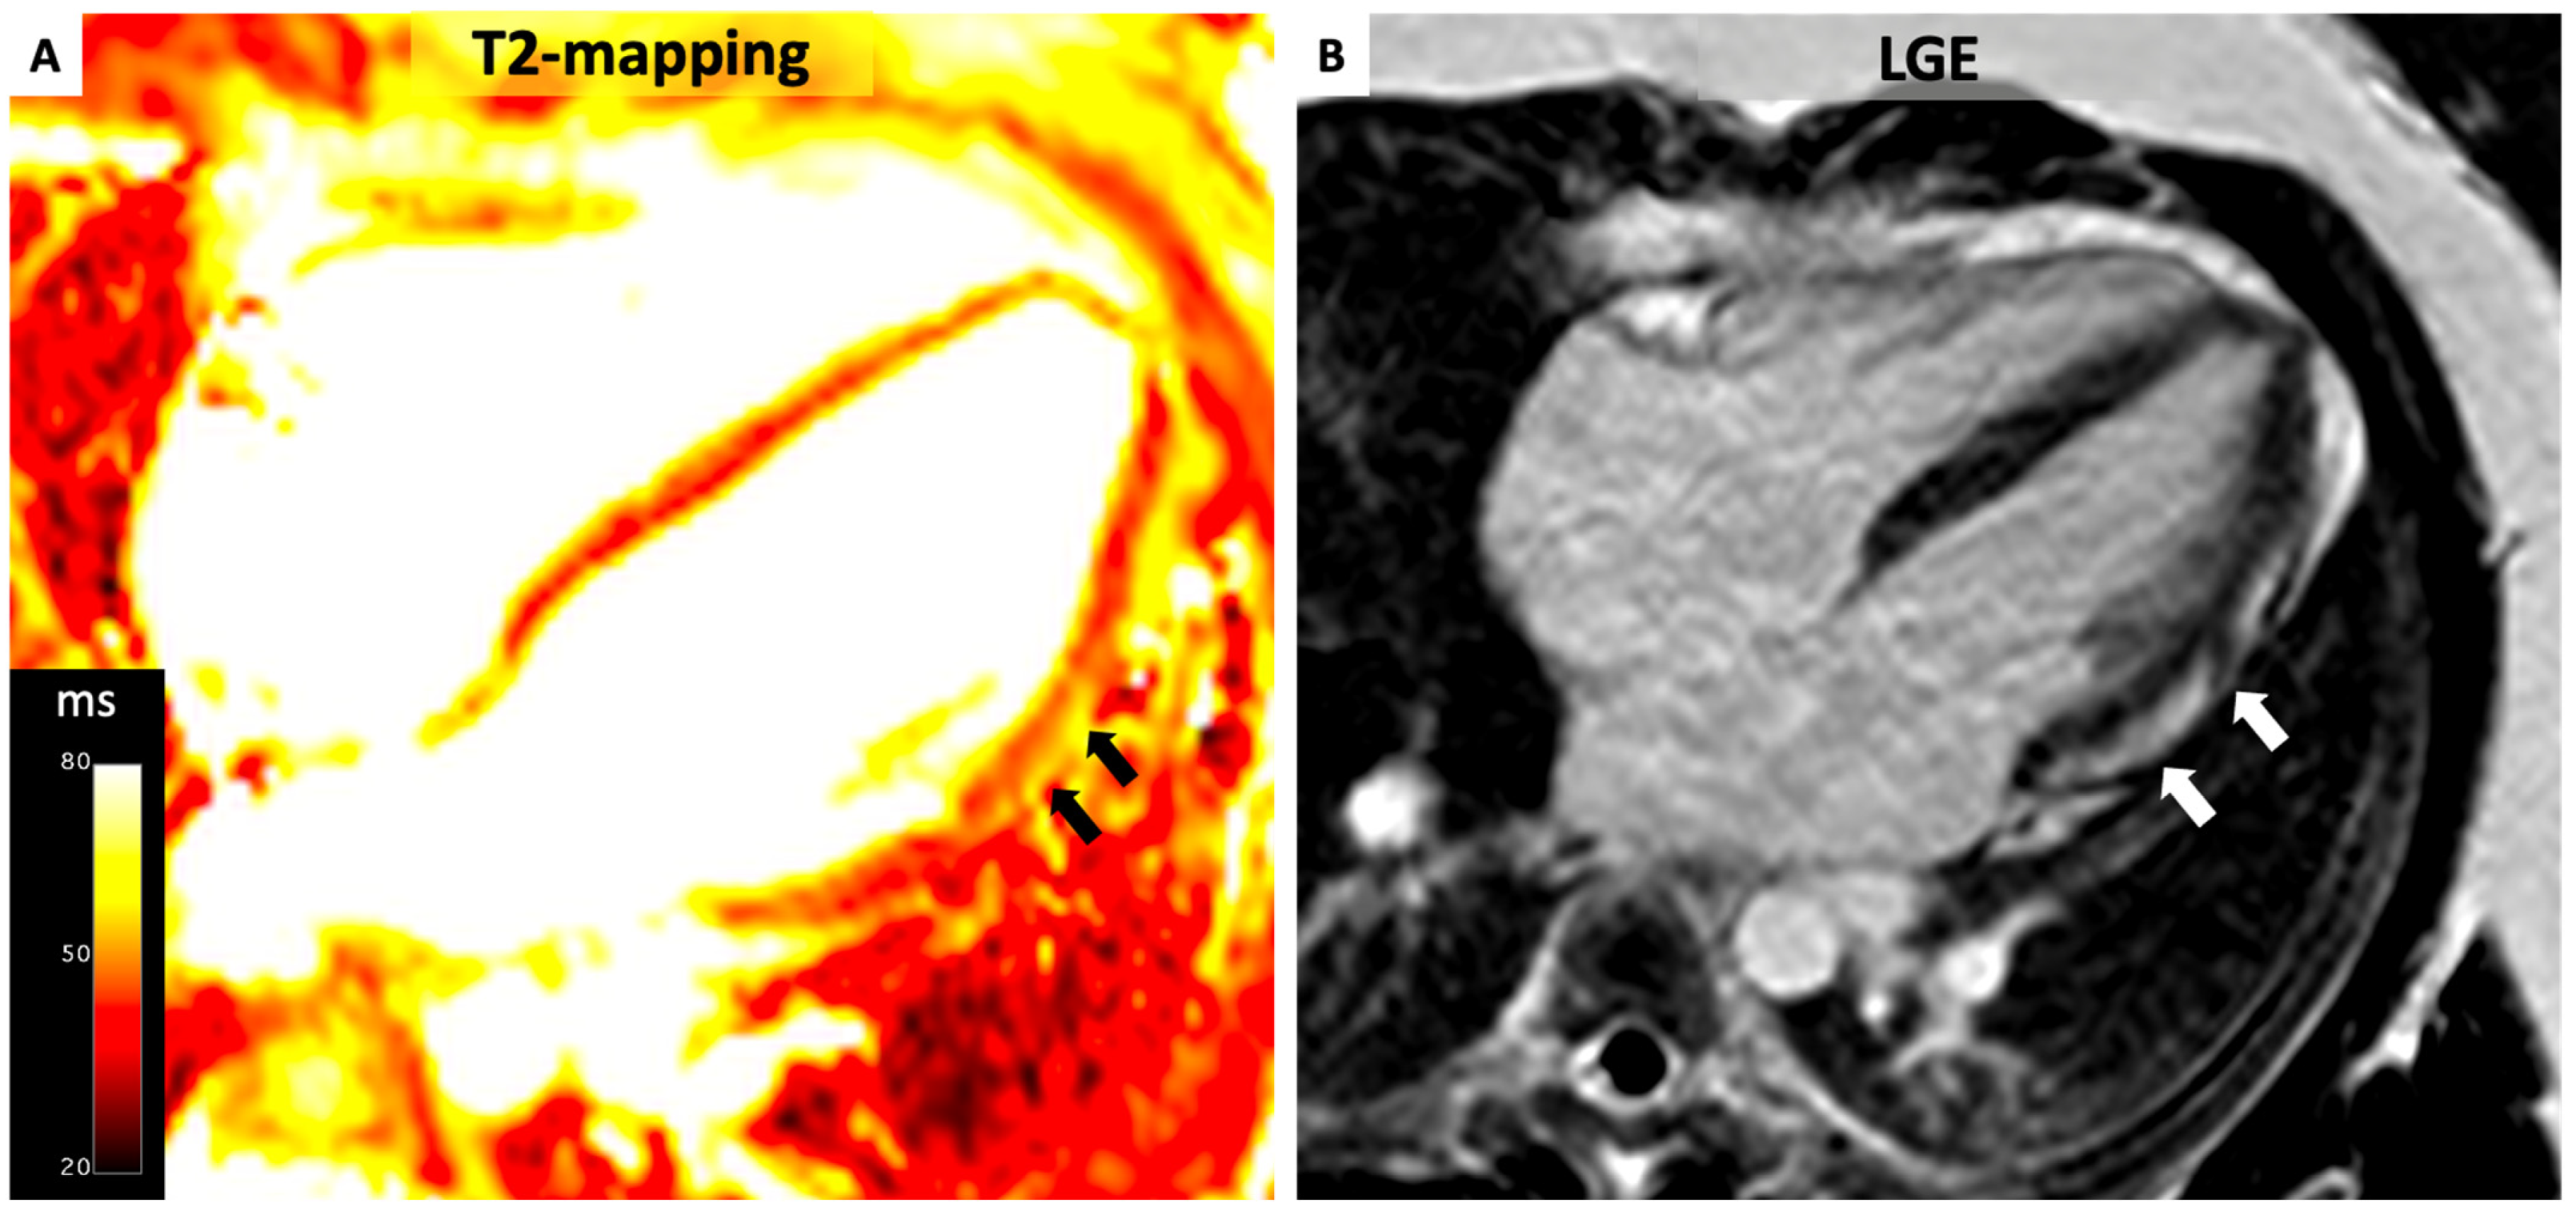

4.3. Myocarditis

- (1)

- Myocardial edema:

- -

- Regional/global increase in T2 signal intensity;

- -

- Regional/global increase in native T2.

- (2)

- Non-ischemic myocardial injury:

- -

- Regional/global increase in native T1;

- -

- Regional/global increase in ECV;

- -

- Regional LGE signal increase.